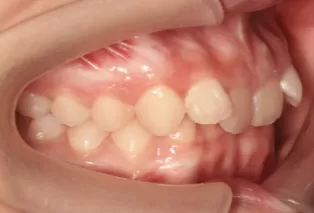

Photos intra-orales